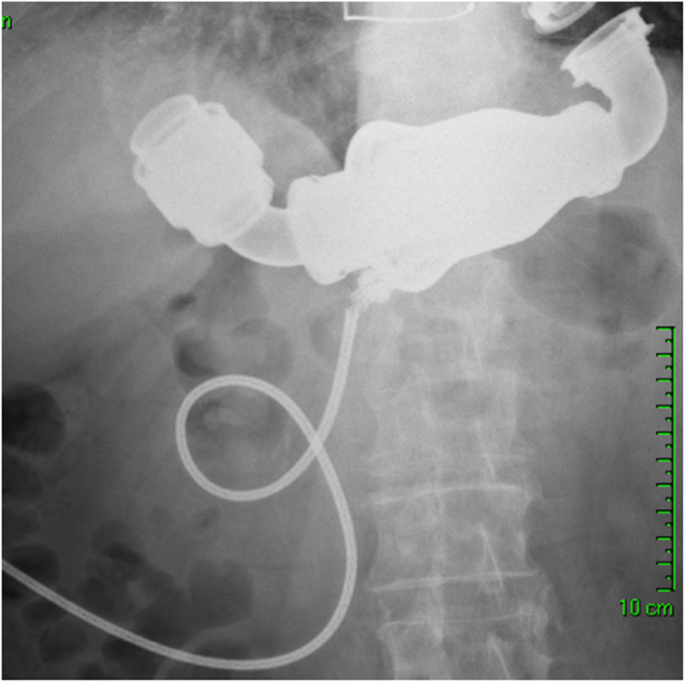

A 75-year-old male patient with severe ischemic cardiomyopathy underwent implantation of HearMate II LVAD and tricuspid valve annuloplasty in December 2013. In April 2014, he was admitted to the emergency room with general weakness, abdominal pain and a red heart alarm in the LVAD system controller. Chest and abdomen X-rays showed a partial disconnection of the driveline from the pump (Fig.1). During preparation for surgery, the LVAD ceased to function and it was decided that the patient undergo urgent pump replacement. There were no operative complications. On post-operative day 3, the patient underwent extubation, and on day 7 in the early hours of the night, the patient died from acute respiratory failure due to aspiration pneumonia. Prior to his death, the LVAD was functioning normally.

Cable damage associated with pump failure is one of the most severe complications after LVAD implantation. This malfunction usually appears at the proximal portion close to the pump body [9]. While an accidental powerful pull on the cable, weight gain and active lifestyle, all reflect improvement of the patient’s clinical condition, it could also be responsible for lead damage. Recently, due to the improvements of the driveline design, the incidence of cable damage has been significantly reduced. Moazem et al. reported a decrease in the incidence of cable damage from 4.2 to 1.2% after modification of the lead design [10]. Patrov et al. reported no case of cable damage after the design improvement in 2012 [9]. Our patient underwent LVAD implantation in December 2013 after the design modification. In our case, the alarm and X-ray allowed for fast diagnosis of the cable damage. Transthoracic echocardiography excluded cannula malposition, significant aortic valve disease and thrombus in the left ventricle. Case 2 patient underwent an uneventful urgent exchange of the main pump body with the remaining inflow and outflow conduits. It is our routine to perform redo median sternotomy in redo cases. Subcostal approach could be associated with less surgical field exposure increased the risk of air embolism due to the lack of access to the outflow graft and aorta. There were no intraoperative complications. Despite the well-functioning LVAD, the patient died on post-operative day 7 due to respiratory failure. In non-emergent cases, pump replacement can be performed safely with operative mortality < 7% [9]. C-shaped tunneling and cable looping of the driveline prevent accidental cable pulling and damage. Transcutaneous energy sources, which are in advanced stages of development, may solve the problem of cable damage completely in the future. Our group together with others performed the first in-human LVAD implantation using wireless energy transfer technology [11].